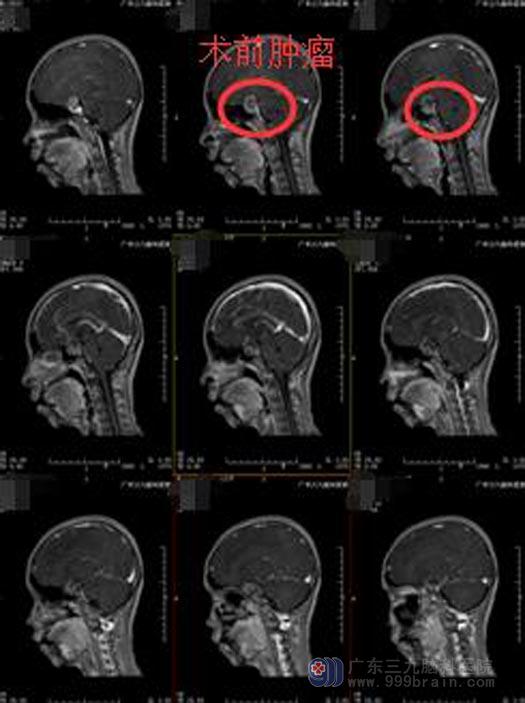

12岁的小何,活泼开朗,学习成绩优秀。近段时间出现右眼视物模糊伴有重影,家人以为是学习压力大用眼过度。在医院眼科就诊,没有发现眼睛有异常,医生建议她去神经外科看看,MR提示鞍区占位,考虑垂体大腺瘤。

在广东三九脑科医院垂体瘤诊疗中心进一步检查后,中心主任鲁明告诉她的家人:小何出现的视力下降、视野偏盲是由于垂体肿瘤向上压迫视交叉所致,必须手术切除。

鲁明主任主刀在全麻内镜下行经鼻碟鞍区垂体瘤切除术,术中再次导航定位,镜下见灰白色肿瘤组织,质软,镜下全切肿瘤。术后小何神志清醒,没有出现尿崩、电解质紊乱、脑脊液漏等并发症,右眼视力视野也在慢慢改善。